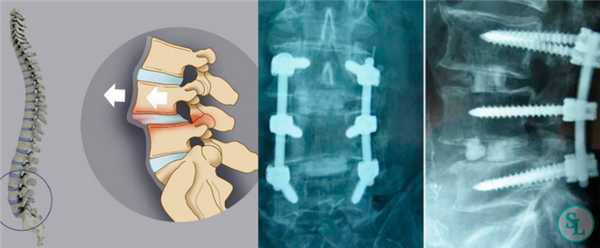

Методика одностороннего заднего трансфораминального межтелового спондилодеза (Тransforaminal Lumbar Interbody Fusion, TLIF), была впервые описана на примере спондилолистеза поясничного отдела позвоночника в 1982 году, благодаря работам выдающегося хирурга Jürgen Harms. Профессор Jürgen Harms всю свою жизнь посвятил исследованию и хирургическому лечению пациентов с патологией позвоночника. Разработанная профессором оперативная техника в лечении нестабильных спондилолистезов, сколиотической деформации позвоночника используется и актуальна по сей день.

TLIF является наиболее эффективным методом лечения пациентов с нестабильным позвоночно-двигательным сегментом позвоночника. Дискэктомия с последующей установкой межтелового кейджа через одно из межпозвонковых отверстий, путем резекции сустава между позвонками, приводит к стабильности передней колонны и создаёт условия для формирования костного блока. Используемый костнопластический материал для создания сподилодеза, заполняет свободные пространства вокруг межтелового стабилизатора и внутри него. Межтеловая стабилизация дополняется транспедикулярной фиксацией, что увеличивает сегментарную стабильность позвоночно-двигательного сегмента и приводит к формированию костного блока позвонков в 98% случаев по данным различных авторов. Цель данной методики — декомпрессия невральных структур и создание косного блока между позвонками.

- Дегенеративный комбинированный стеноз позвоночного канала с клиникой односторонней радикулопатии. Рисунок 1.

Техника заднего трансфораминального межтелового спондилодеза:

После скелетирования позвонков устанавливается ранорасширитель. Доступ к межпозвонковому диску осуществляется с той стороны, где у пациента имеется клиническая картина радикулопатии. Если клиники радикулопатии нет, то сторона доступа значения не имеет. На примере дегенеративного спондилолистеза L4 позвонка будет разобран метод стабилизации. При помощи костных кусачек и долота удаляется межпозвонковый сустав L4-L5 справа. Рисунок 6. На противоположной стороне временно тампонируют рану после скелетирования.